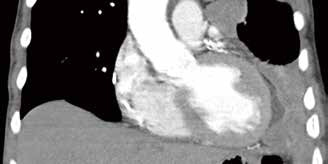

英国研究者Bayman等报告,对于恶性胸膜间皮瘤(MPM)患者,手术部位常规使用预防性胸壁照射不降低转移率。(J Clin Oncol. 2019年3月28日在线版 doi: 10.1200/JCO.18.0167)MPM…